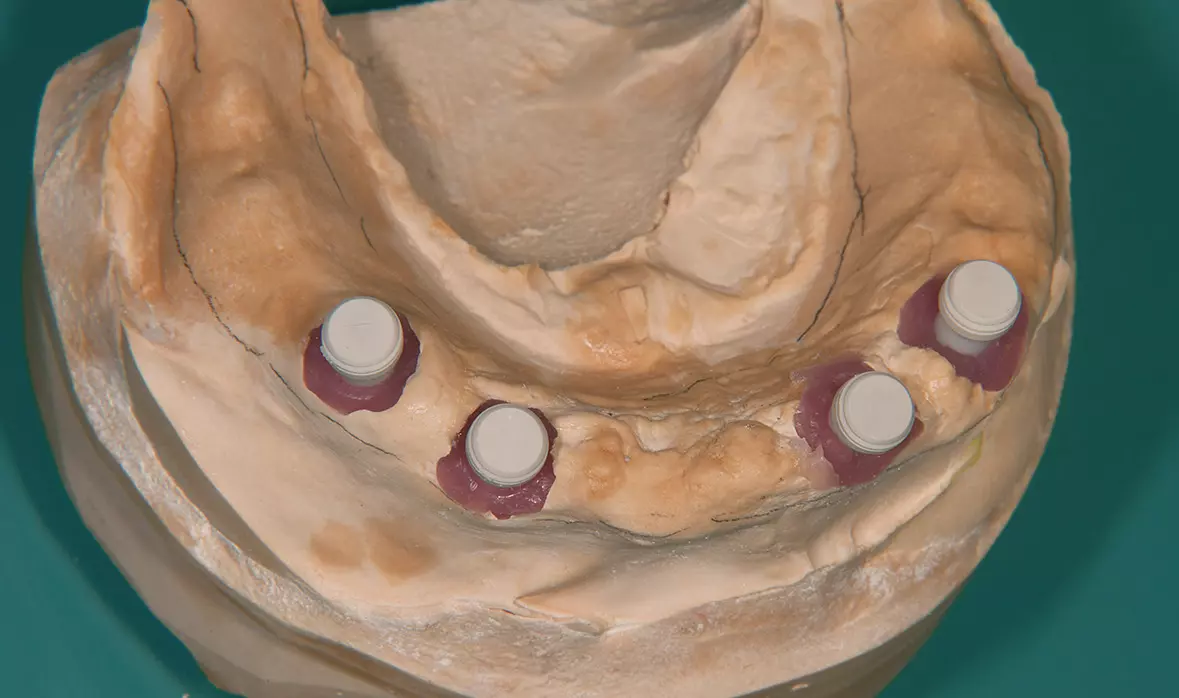

Abb. 23: Das Meistermodell. Dr. Michael Leistner

Abb. 23: Das Meistermodell.